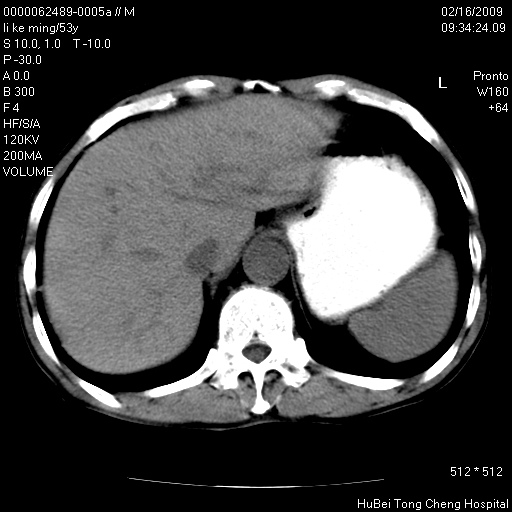

以下是引用卜一在2009-2-16 16:13:00的发言:[br]胰胆管扩张,末端明显狭窄 梗阻,胰头及十二指降段壶腹部结构紊乱。多考虑:十二指降段壶腹部癌!

以下是引用dyqct在2009-2-16 16:58:00的发言:[br]胰头内斑点状及结节状高密度影是钙化灶还是其它?以往做过什么治疗?

以下是引用zsl6918在2009-2-17 8:48:00的发言:[br]符合胰头癌侵犯十二指肠。